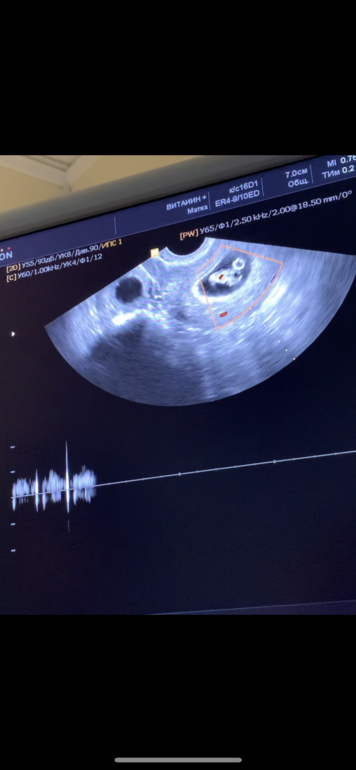

Сделала узи 8+6 недель

Беременность- 1 триместр ( только до 10 недель)Я чуть не заплакала когда дали послушать, такое спокойствие сразу не смотря на бешенный ритм сердцебиения.

Главное все хорошо, немного отстаю по срокам но у меня всегда поздняя овуляция

Она крутила крутила я вообще не поняла где ребёнок но она сказала все хорошо, вернее я поняла где ребёнок но там ещё рядом какой то круг она сказала это головной мозг и тогда я поняла что я ничего не поняла))

Вот это Мешочек да ?